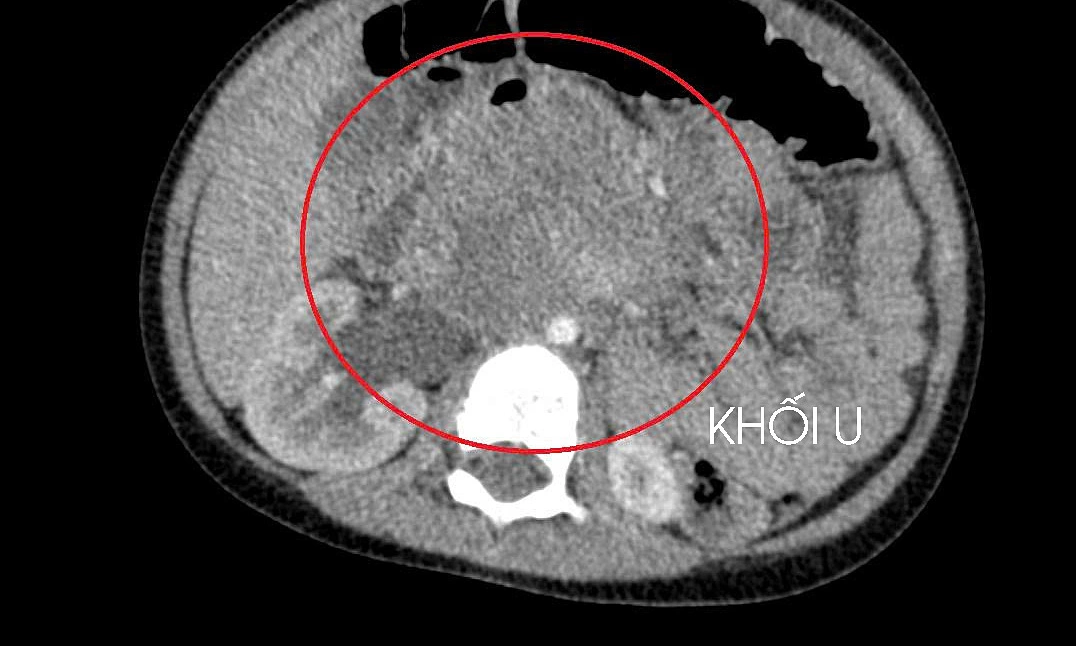

10일 흥붕 종합병원 의사들은 3세 아동이 장기간 복통을 호소했으나, 가족이 외곽 지역에 거주하여 의료 접근이 어려웠다고 전했다. 아동이 병원에 입원했을 때, 종양이 신장을 압박하고 있었으며, 고환암 생검 결과 간과 폐로 전이된 상태로 확인되었다. 이는 아동의 고환이 출생 시부터 음낭이 아닌 복부에 위치하여 명확한 증상 없이 서서히 성장했기 때문이라고 밝혔다.